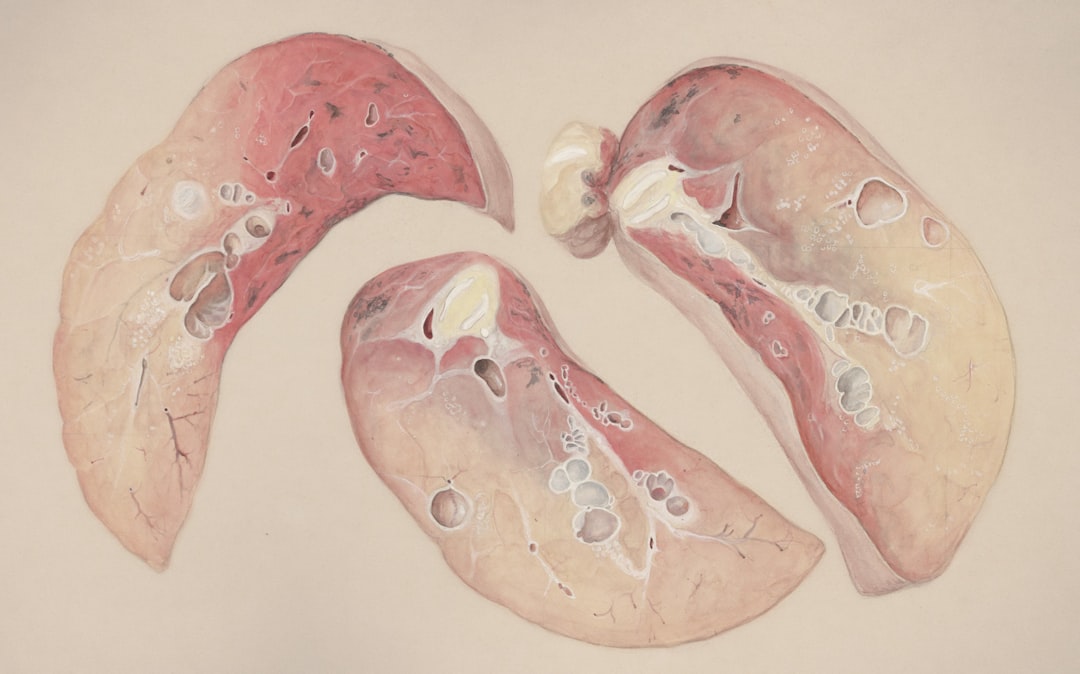

의료기관에 도착하면 우선적으로 필요한 검사를 진행하게 됩니다. 이러한 검사들에는 흉부 X선이나 CT 촬영 등이 포함될 수 있습니다. 이후 검사를 바탕으로 가장 적절한 치료 방법을 의사가 제안할 것입니다. 기흉 치료는 상황에 따라 다르므로, 전문가의 의견을 존중하고 따르는 것이 필요합니다. 기흉 검사의 중요성을 간과하지 않고, 모든 단계를 놓치지 않아서 내 건강을 지키는 것이 좋겠죠!